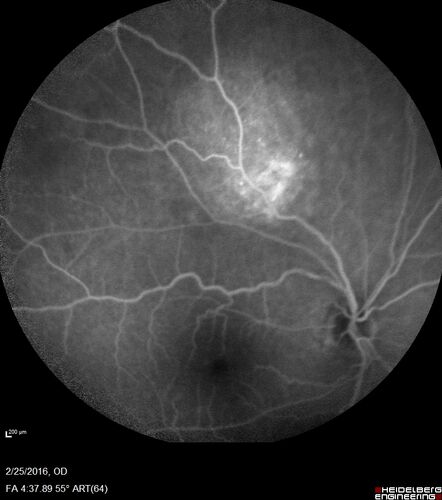

Amelanotic Choroidal Nevus - Multimodal Imaging

61 year old man with amelanotic choroidal nevus. Vision Normal - Stable over 4 years.